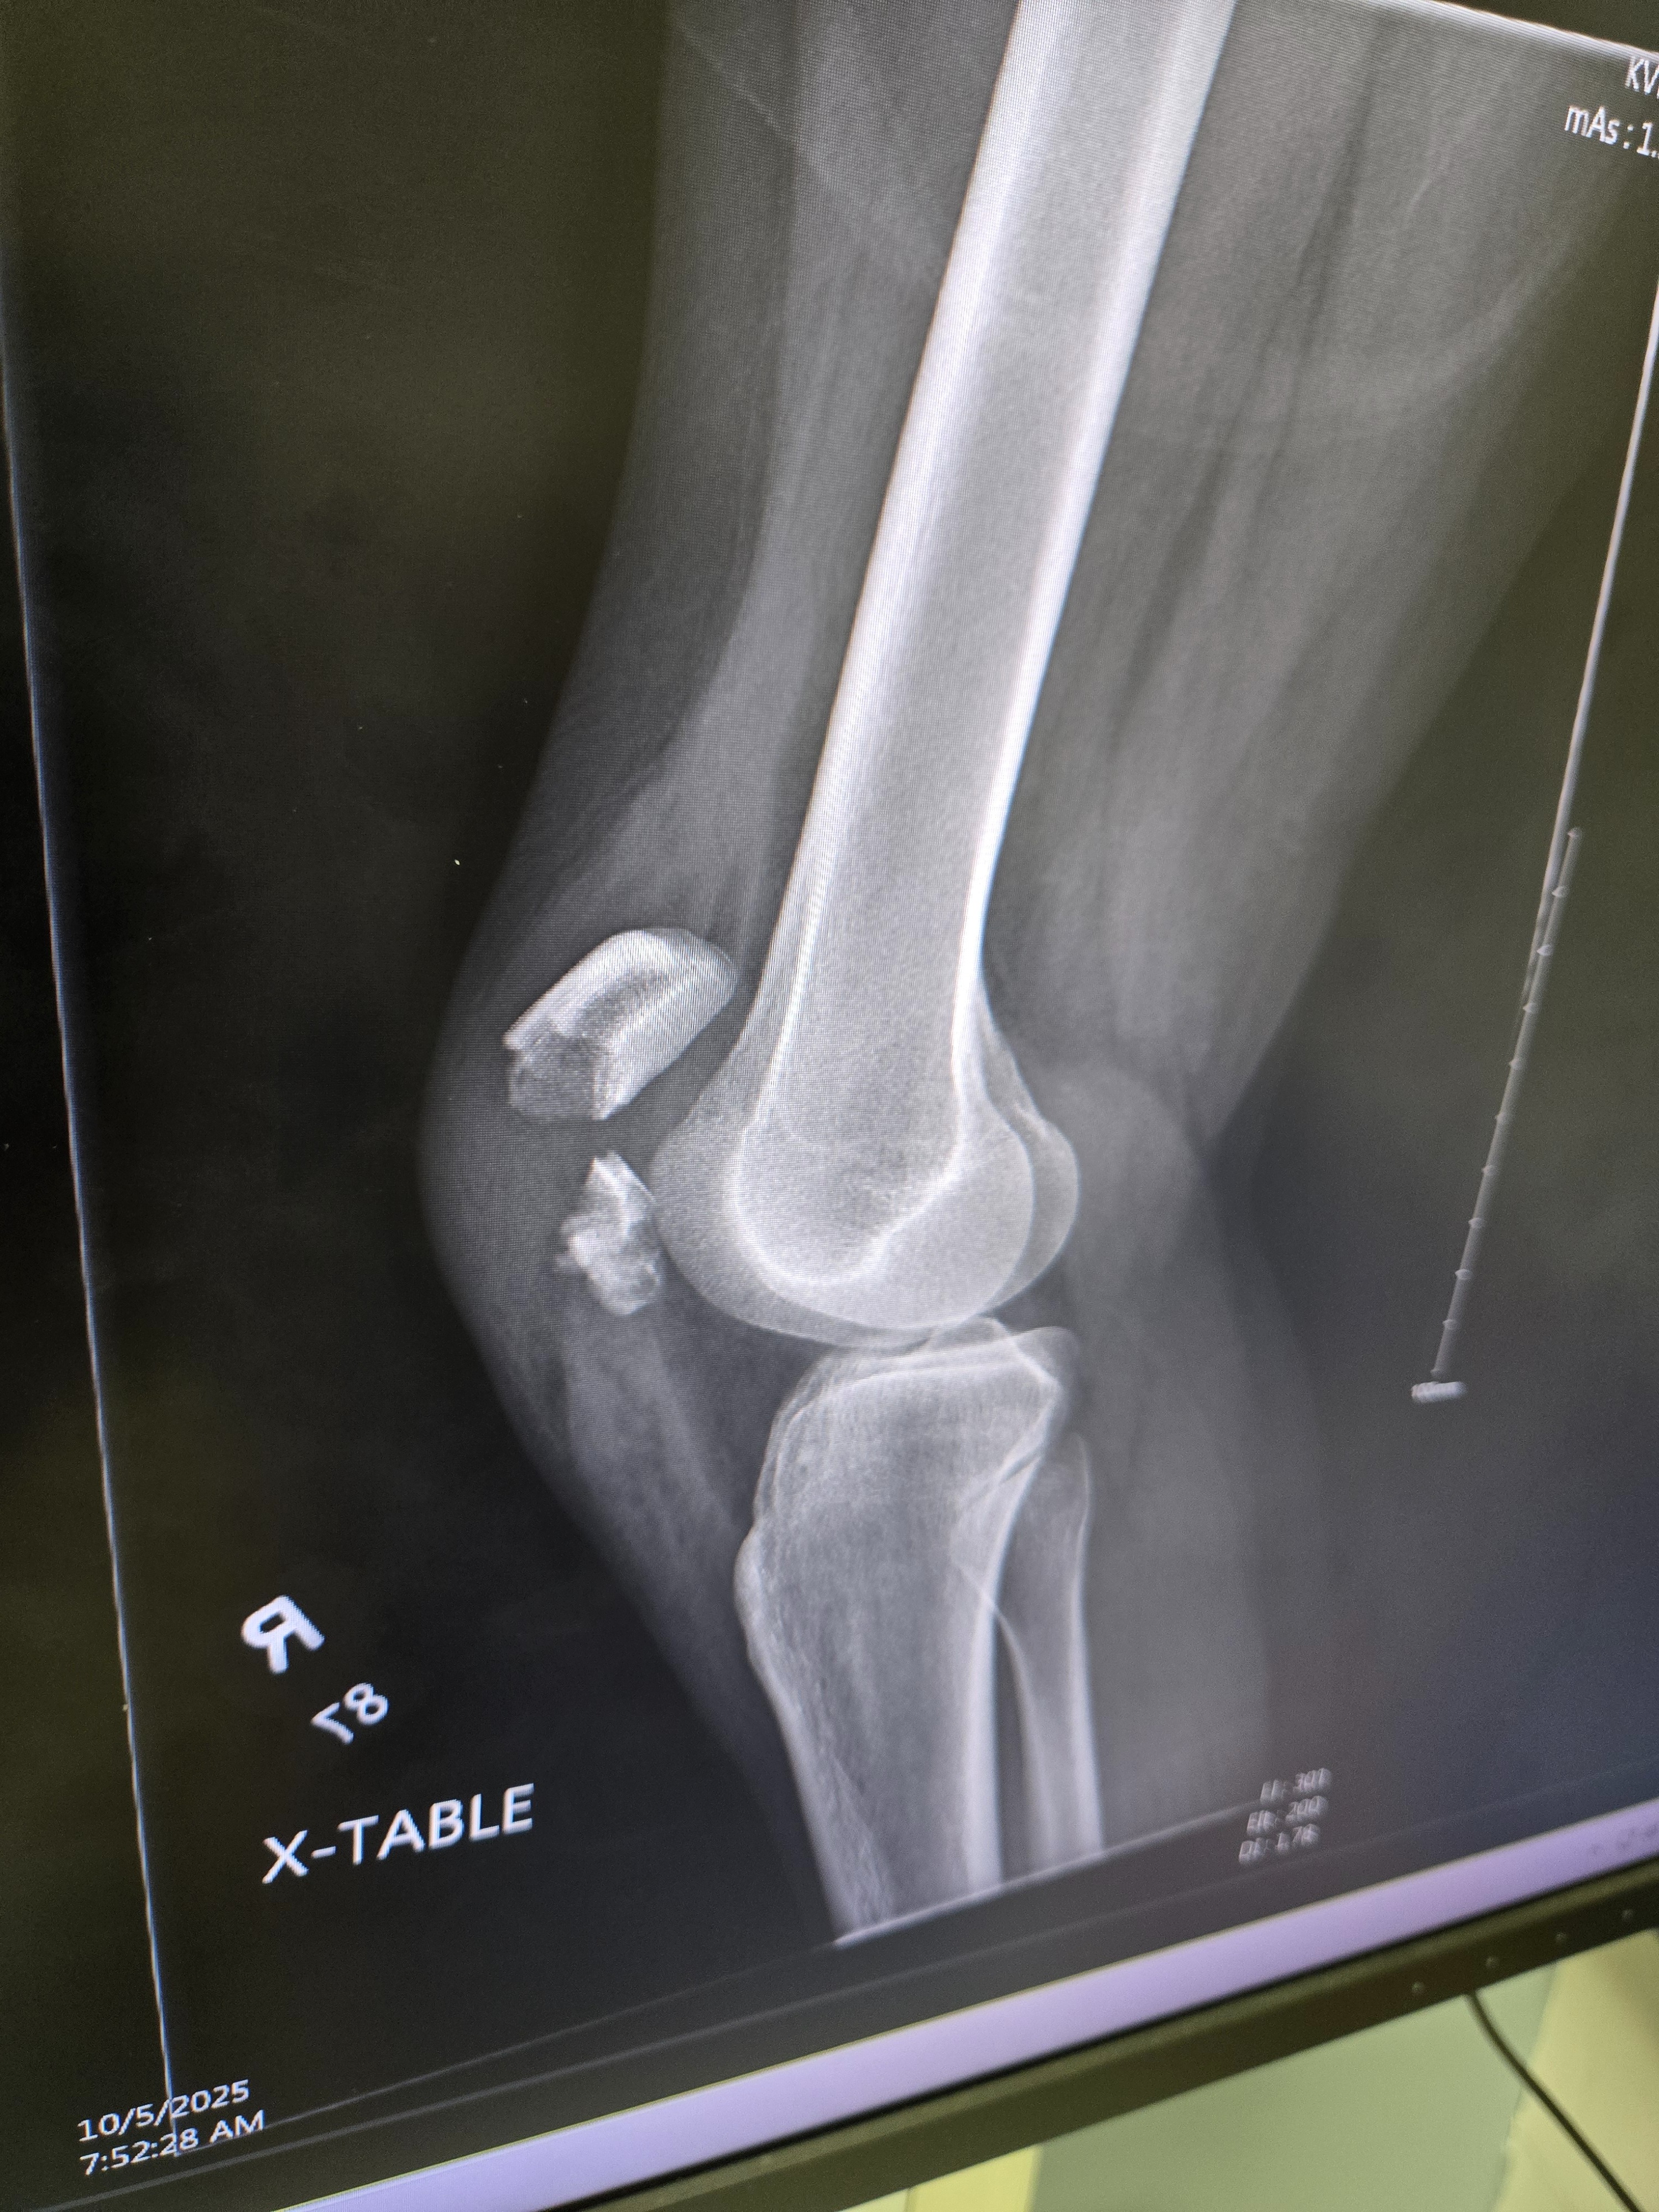

I SURVIVED!!!! My name is Rachel Blackowski, 31 years young.. I was in a severe car accident on Oct 4th . Spent a week in the hospital and have been in rehab. Broken wrist on the left hand (& I'm a lefty) Broken right leg, ankle and knee, non weight bearing injuries for both have me in the wheelchair for an estimated 12 weeks. Have gone through 3 surgeries so far with more to come. Looking at a 6-8 months minimum recovery. Unable to work to provide living wages & owe medical bills. Usually I would be too stubborn & prideful to ask for help ... but this has humbled me to realize I need to lean onto others in my time of need and it is okay. Thank you for any help offered.